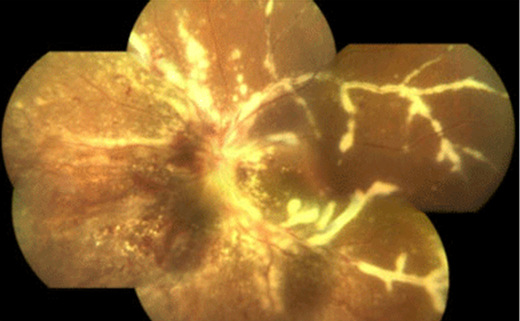

Inflamação nos vasos da retina (vasculite)